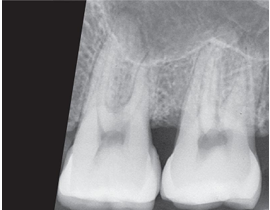

What is the problem with this UNDERDEVELOPED FILM X-ray?

Appears light, Inadequate development time, Developer solution too cool, Inaccurate timer or thermometer, Depleted or contaminated developer solution

How would you resolve this UNDERDEVELOPED FILM X-ray?

Check development time, Check developer temperature, Replace faulty time or thermometer, Replenish developer with fresh solutions as needed